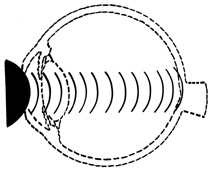

COUP AND CONTRECOUP

Courville24,25 introduced the concept of coup and contrecoup injury to explain brain damage caused by blunt trauma to the head. Coup refers to local trauma at the site of impact. Contrecoup refers to injuries at the opposite side of the skull caused by shock waves that traverse the brain. Foci of brain damage are found along the path of the shock waves, especially at interfaces of tissues of different density. The greatest difference in density is between the brain and the skull, and it is here that the most severe damage occurs. Wolter later used these concepts to explain eye injuries.26 Examples of coup injuries are corneal abrasions, subconjunctival hemorrhages, choroidal hemorrhages, and retinal necrosis (Fig. 1). The best example of a contrecoup injury is commotio retinae (Fig. 2). These injuries are discussed later in this chapter.

Fig. 2. Contrecoup injury. When a blunt object strikes the eye, shock waves traverse the eye to strike the posterior pole.

FIG. 3. When the eye is compressed along its anterior-posterior axis, it expands in its equatorial plane (small arrows), causing severe traction at the vitreous base (large arrows).